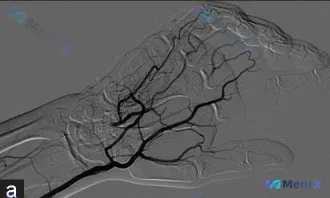

- 影像资料(动脉造影):

- 桡动脉血流非常快,而且是完全顺行的

- 显影的血管看起来都挺好,没有明显的狭窄、闭塞或者对比剂外溢

- 掌弓结构完整,侧支循环看起来也不错